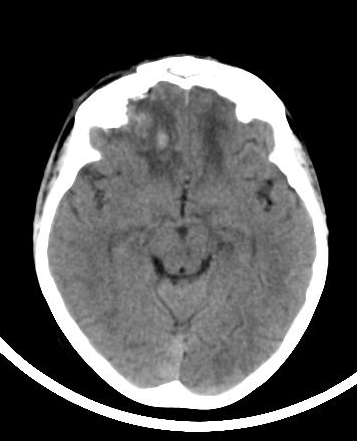

• Gãy xương phức tạp

Gãy xương Le Fort (Le Fort fracture classification)